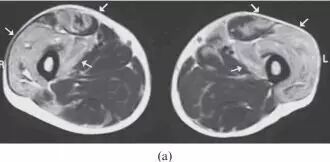

![]()

图24.骨骼肌损伤和肌坏死。 该患者,在坠落后发生的右大腿中的受污染伤口导致感染性肌坏死。 (a)轴向T2加权MRI图像显示肿大的内收肌和股二头肌----(肌肉)由于水肿扩散高信号强度。 在大收肌(箭头)中看到中心区域与流体聚集相一致。 (b)冠状动脉脂肪抑制T2加权磁共振成像显示弥漫性水肿在大腿近端的后房(箭头)。 其信号空隙肌内气体被看作指示严重感染(气性坏疽)的存在(箭头)。 感染区域的培养物显示破伤风杆菌。